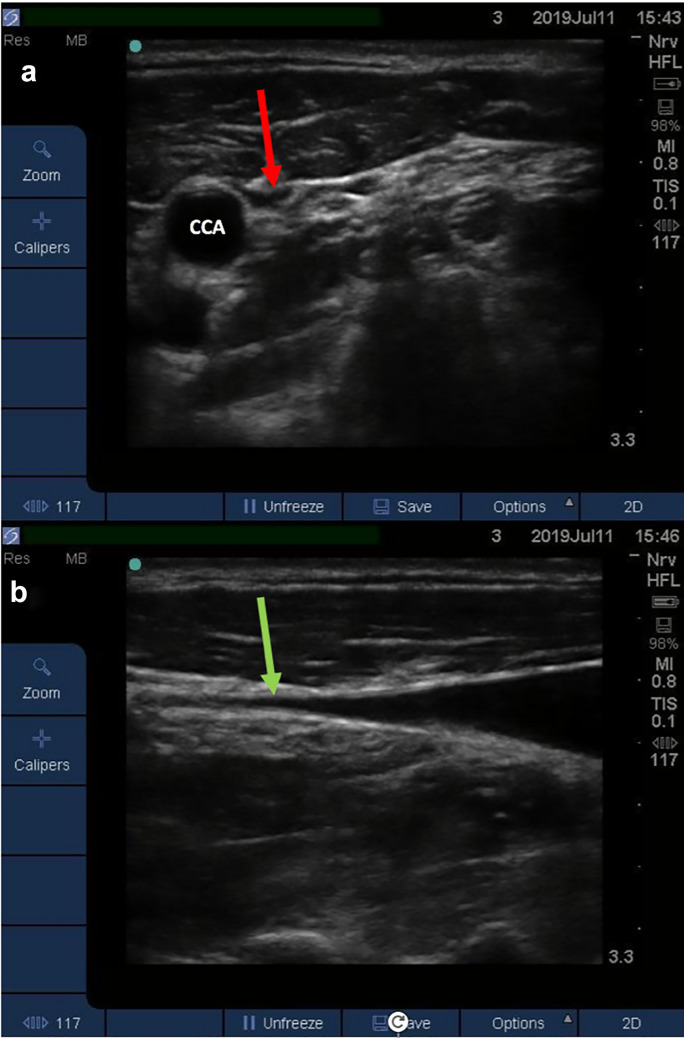

Prior to measuring both U-JVP and CVP post-operatively, the central line transducer was placed at the phlebostatic axis in line with the patient’s right atrium. The central line was calibrated by zeroing the transducer relative to atmospheric pressure. The line was flushed to ensure there was a continuous column of fluid. For blinding purposes, estimation of the U-JVP was carried out first prior to invasive CVP measurement. A Sonosite NanoMaxx 13 MHz linear transducer or Sonosite S-Nerve 13 MHz linear transducer was used for insonation. The probe was placed on the patient’s neck in the transverse plane, proximal to the clavicle on the contralateral side to the inserted central line. The IJV was located whilst applying minimal pressure to the skin. The probe was moved superiorly until the vein was seen to collapse (Fig. 2a). The angle of the bed on which the patient was lying was adjusted to allow visualisation of the collapse point in the middle of the patient’s neck. This ensured that the vein was not being splinted open by negative intrathoracic pressure as it entered the thoracic cavity. The probe was then rotated into the longitudinal axis to identify the point of venous collapse upon end-expiration (Fig. 2b). The venous collapse point was then marked. The investigator then observed the directly measured CVP on the monitor and recorded the value immediately.

Fig. 2.

a Transverse view of a collapsed IJV. The red arrow points towards the collapsed IJV. The higher blood pressure within the CCA means the vessel does not collapse. b Longitudinal axis of the IJV. The IJV tapers until reaching the point of collapse. The green arrow indicates the point at which the vein was considered collapsed